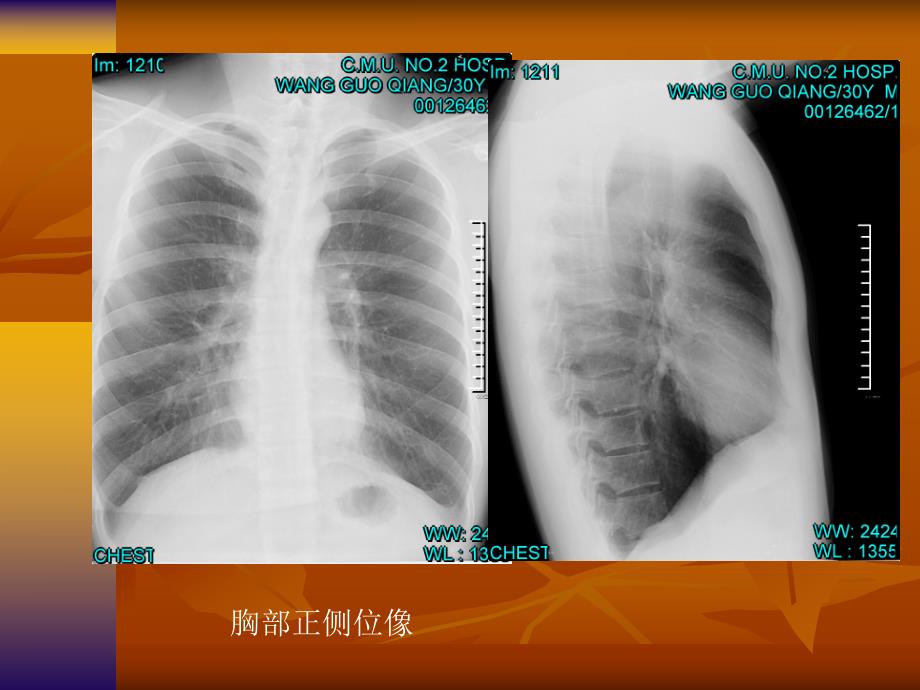

胸部正侧位像胸部正立侧卧位肺泡蛋白沉积症 肺泡蛋白沉积症是咋回事?肺泡蛋白沉积症是咋回事?北京市呼吸疾病研究所郭伟张洪玉肺泡蛋白沉积症是一种以蛋白样物质沉积于肺泡和细支气管腔为特征的呼吸科疾病。发病原因可能与感染、肺泡细胞功能有缺陷及对粉尘等吸入物的异常反应等因素有关。病人常感活动后气短,同时伴有轻微咳嗽、无力、消瘦、食欲差;查体常无明显异常,严重的患者可有口唇、指甲等发紫以及眼底出血。本病的治疗主要是针对性地排出沉着于肺泡表面的蛋白样物质。近年来有人认为一旦诊断为肺泡蛋白沉积症,可立即做支气管肺泡灌洗。北京朝阳医院呼吸疾病研究所2001年7月曾收治了一名62岁男性患者,因咳嗽、气短1年,加重半个月收入院。曾多次在外院就诊,根据胸片诊断为肺炎,但消炎治疗效果不明显。入院后明确诊断为肺泡蛋白沉积症。给患者全身麻醉后,用呼吸机做单侧肺通气,然后用37生理盐水反复灌洗肺泡,经过有效灌洗,抽出的灌洗液从一开始呈豆浆样逐渐变得清亮。两肺灌洗间隔时间为一周。灌洗治疗后患者感觉咳嗽、气短等不适明显好转,活动能力增强,可以在室内自由活动及自理生活。肺泡蛋白沉积症纵隔血肿纵隔血肿胸部投影胸部正常X线表现正常胸部正侧位像肺动脉肺静脉心脏投影肺动脉肺静脉正面观后面观气管分叉平面气管分叉平面中间支气管平面中间支气管平面